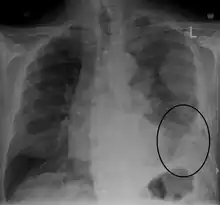

| CT scan showing a left sided mesothelioma with an enlarged mediastinal lymph node | |